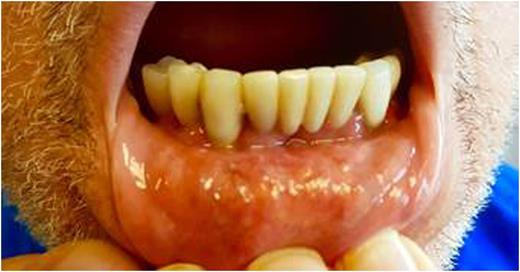

Case: A 69 year old male presented to his dentist with pain and gingival hyperplasia in the left maxilla which was treated with scaling of the gums. Following this, the patient developed worsened pain, which was treated with the extraction of 3 upper molars. The pain continued to worsen and the dentist prescribed a course of amoxicillin. Three weeks from his initial dentist visit, the patient went to his family physician for a routine checkup. Labs showed elevated leucocyte counts (54000/dl) and he was referred to hematology for a bone marrow evaluation. Physical examination of the oral cavity found hyperplasia of the gingiva with ulceration and necrosis of the left maxillary gingiva accompanied by severe halitosis and pain Bone marrow findings were consistent with AML with monocytic differentiation (51% blasts).According to AFB classification the AML fell in the M4 category. In collaboration with infectious disease consultation it was decided to treat oral infection and defer induction chemotherapy until the infection was controlled. The patient was started on ampicillin/sulbactam with routine antimicrobial prophylaxis, with resultant improvement in oral pain and halitosis. After 4 days of antibiotic therapy, the infection was controlled and chemotherapy with daunorubicin and cytarabine was started on day 5 of admission.

Discussion: The case demonstrates the importance of early identification of gingival hyperplasia in AML (AFB classification M4 and M5), especially since it is one of the earliest signs of AML. The familiarization of dental health professionals with oral manifestation of systemic diseases can significantly reduce patient morbidity by early diagnosis and intervention. In such cases, during the course of chemotherapy, any spontaneous or provoked dental pain, swelling, or evidence of purulent discharge must be considered as an odontogenic infection until proven otherwise as the inflammatory response may be blunted due to myelosuppression. The clinical signs of erythema, swelling, and purulence are highly variable, and the absence of these features is insufficient to rule out infection.